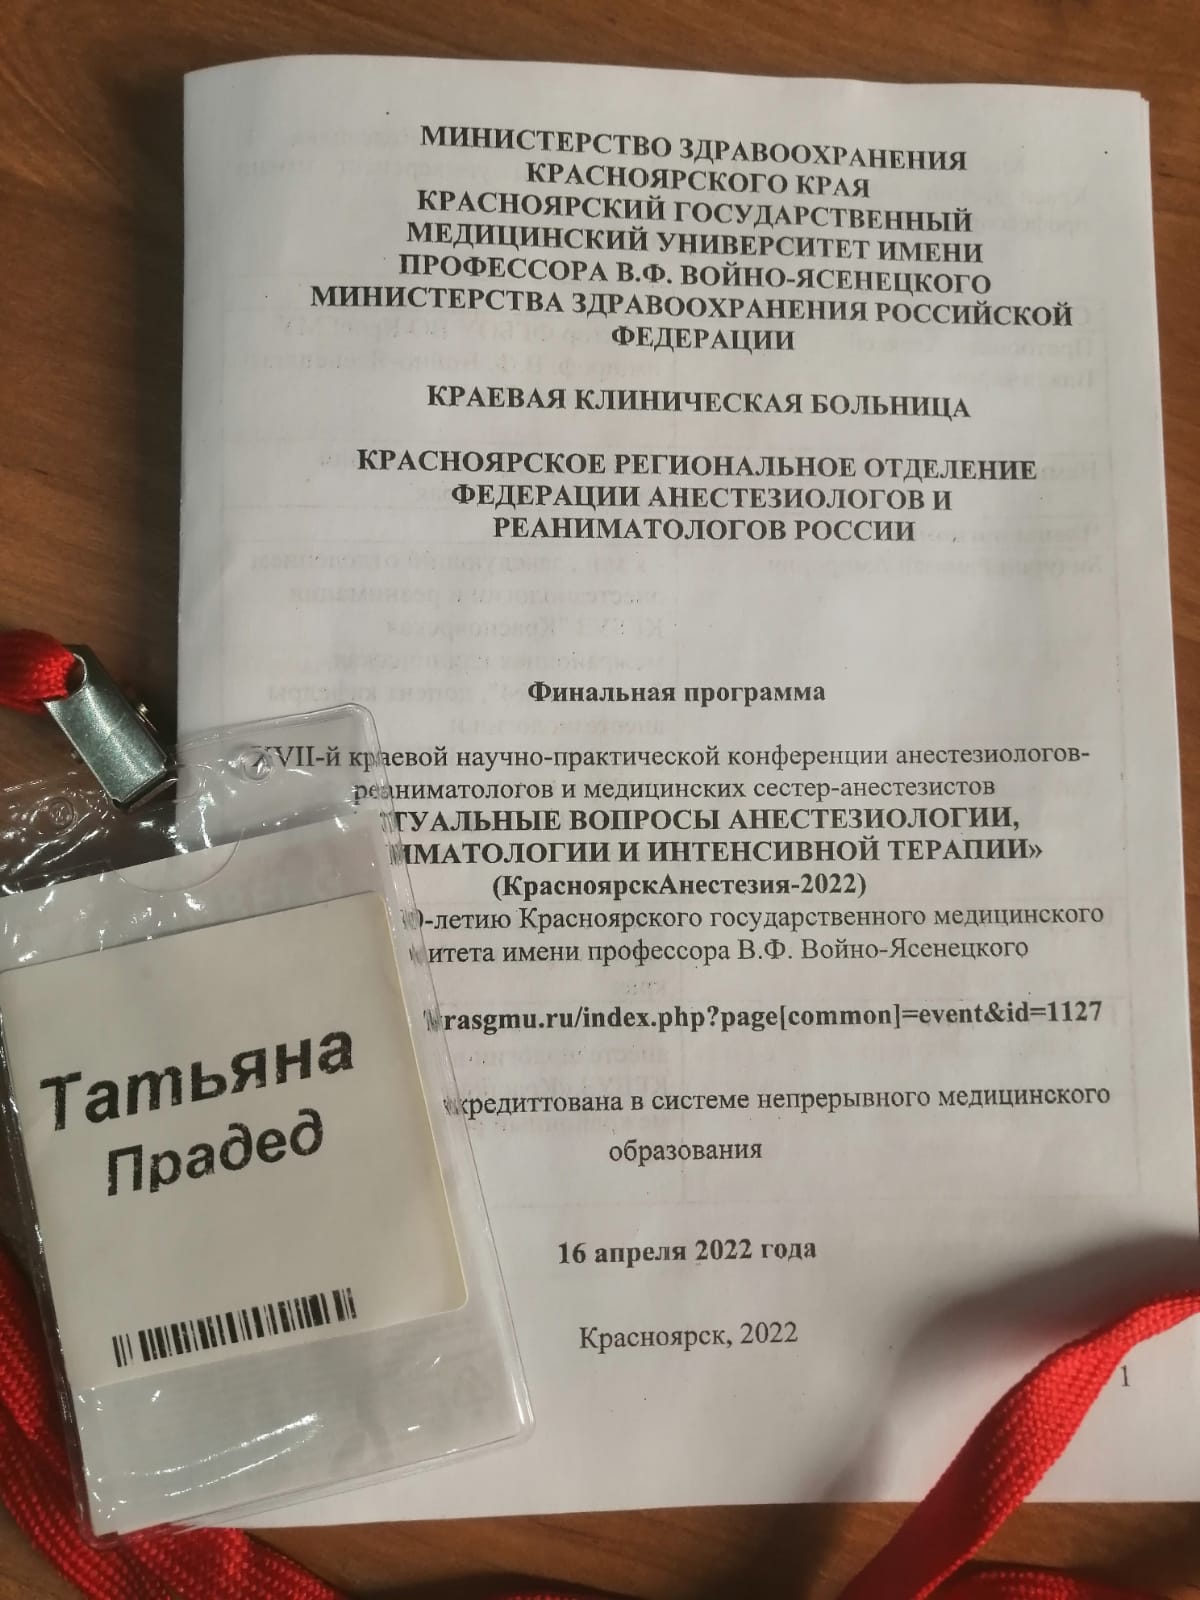

17.04.2023

16 апреля состоялась XVIII Краевая научно-практическая конференция анестезиологов-реаниматологов.

КГБУЗ «КМКБ № 4» примет участие в проведении XVIII Краевой научно-практической конференции анестезиологов-реаниматологов.

18.04.2022

Сотрудники «КМКБ №4» выступили на XVII краевой научно-практической конференции анестезиологов-реаниматологов и медицинских сестер-анестезистов.